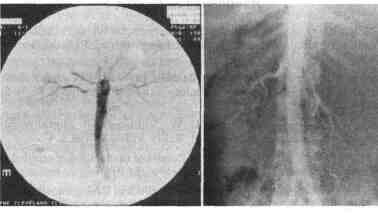

• Выявление опухолевого тромба (почечно-клеточный рак). • Окончательное подтверждение тромбоза почечной вены • Определение содержания ренина в крови почечной вены при реноваскулярной гипертензии ![]() Рис. 4-1. Слева Цифровая субтракционная ангиограмма, на которой определяется билатеральный стеноз почечных артерий Справа Стандартная катетеризационная ангиограмма на которой определяется смещение левой почечной артерии вниз за счет расположенного слева большого гиповаскулярного объемного образования надпочечника 19. Назовите три ангиографические методики.